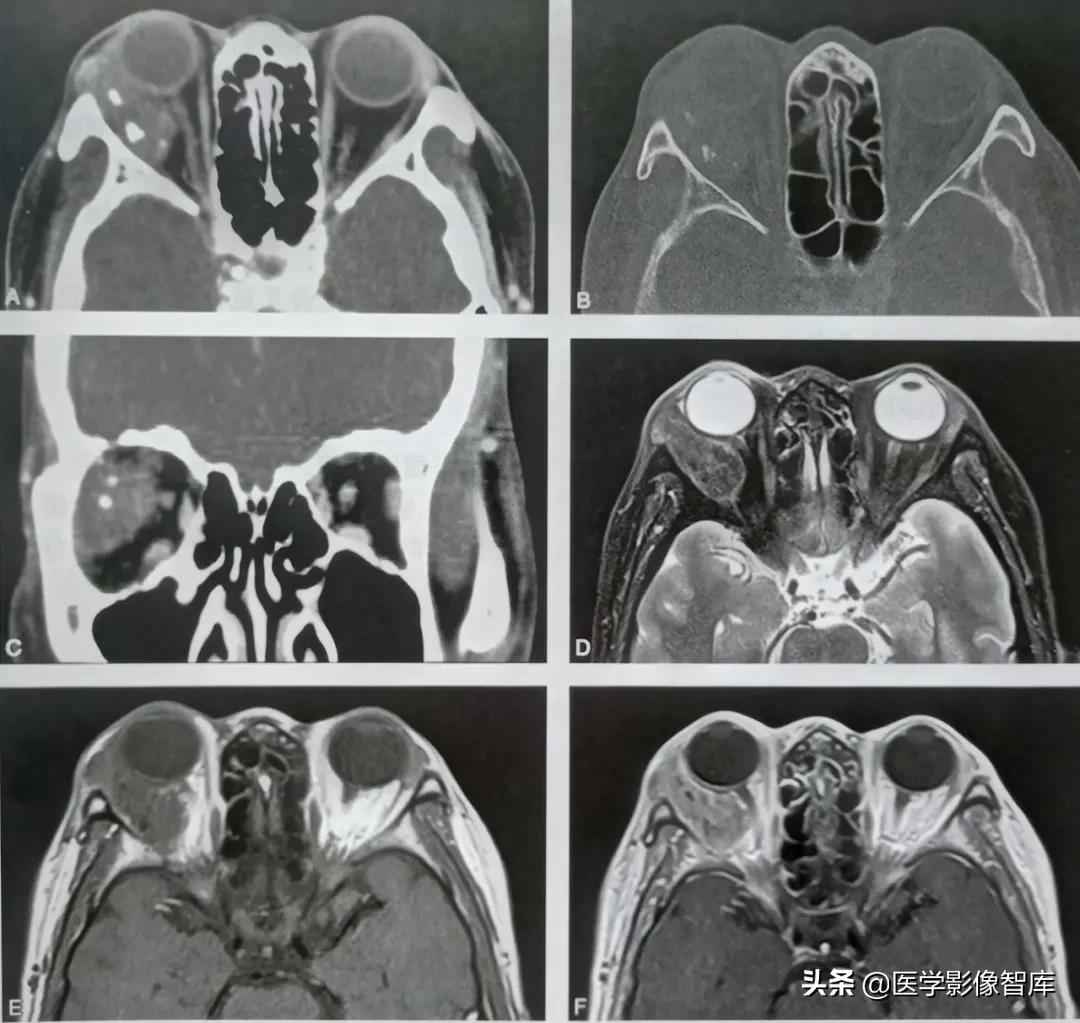

患者,女,54岁。右眼球突出半年(如图)。

右侧眼眶淀粉样变性

横断位CT软组织窗(图A)示右侧眼眶软组织肿块,形态不规则,边界清晰,肿块内见点状钙化;骨窗 (图B)示右侧眼眶外侧壁形态良好,未见破坏。冠状位CT软组织窗(图C)示肿块位于外上象限。横断位T2WI和T1WI(图D和图E)示肿块在T1呈等信号,T2呈不均匀低信号。橫断位增强T1WI(图 F)示肿块明显不均匀强化。